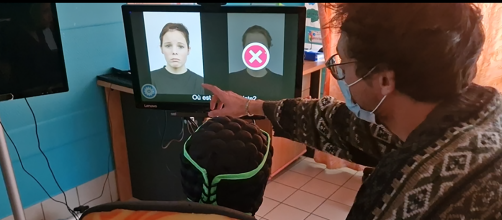

Mieux évaluer les personnes polyhandicapées

Face au polyhandicap, des capacités d’apprentissage insoupçonnées